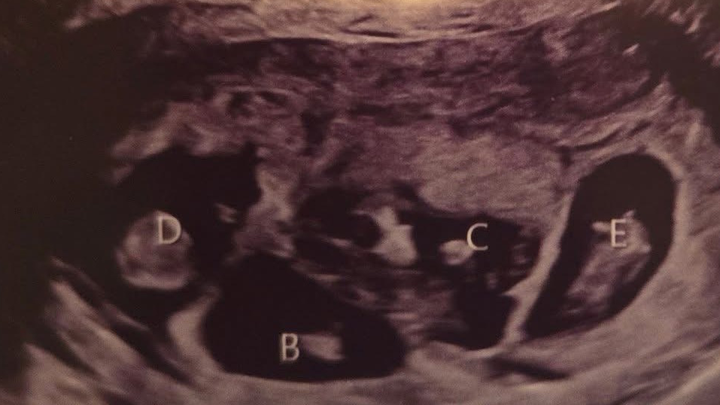

Jess is an amazing mother to her two young daughters, Hannah and Brooke, and a dedicated wife to the love of her life, John. They recently decided to expand their family and went through some fertility treatments. It was not IVF. She spontaneously released five eggs and all five were fertilized. Once again, this was not an intentional thing, nor is it something that could’ve been predicted. So now she is almost 20 weeks pregnant with quintuplets! For those of you who don’t know, that is five babies tucked safely away in her belly. The babies are thriving; they’re growing at appropriate rates, and as of right now, there’s no sign of major complications.